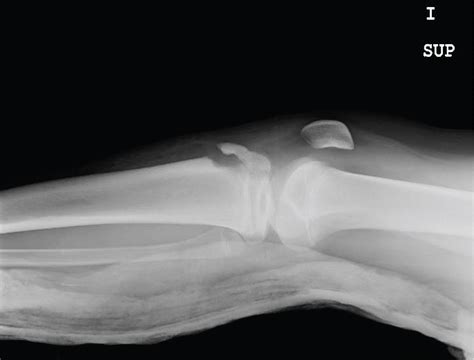

To confirm the diagnosis, medical professionals typically utilize imaging studies. X-rays are the gold standard for visualizing the displaced bone fragment and determining the severity of the fracture. In more complex or comminuted cases, an MRI may be ordered to assess the condition of the surrounding soft tissues, including the patellar tendon and menisci.

• Deformity: A visible or palpable gap or bump may be present at the site of the injury.

Orthopedic surgeons often categorize these injuries based on the Ogden classification system, which helps guide treatment decisions. This classification ranges from simple, non-displaced fractures to complex injuries that extend into the knee joint.